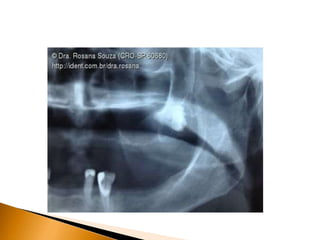

• 36.

A maioria dosesquemas de classificação é baseada na análise de radiografias. 1. A radiografia panorâmica mostra a imagem mais acurada da anatomia da região e é a escolha para o planejamento de terceiros molares impactados. 2. A radiografia periapical bem posicionada é adequada, desde que a maior parte do dente impactado esteja visível junto a importante anatomia adjacente. 3. A tomografia computadorizada é útil em casos onde as raízes de terceiros molares inferiores aparecem muito próximas ou sobrepostas ao canal alveolar inferior na radiografia panorâmica.

 Terceiros molaresinferiores impactados frequentemente tem raízes que estão superpostas ao canal alveolar inferior nas radiografias.  Apesar de o canal estar quase sempre na face distal do dente, ele ainda pode estar na proximidade das raízes.  Se o final da raiz do dente aparece próximo ao canal alveolar inferior na radiografia, o cirurgião deve tomar cuidado especial para evitar lesão ao nervo.